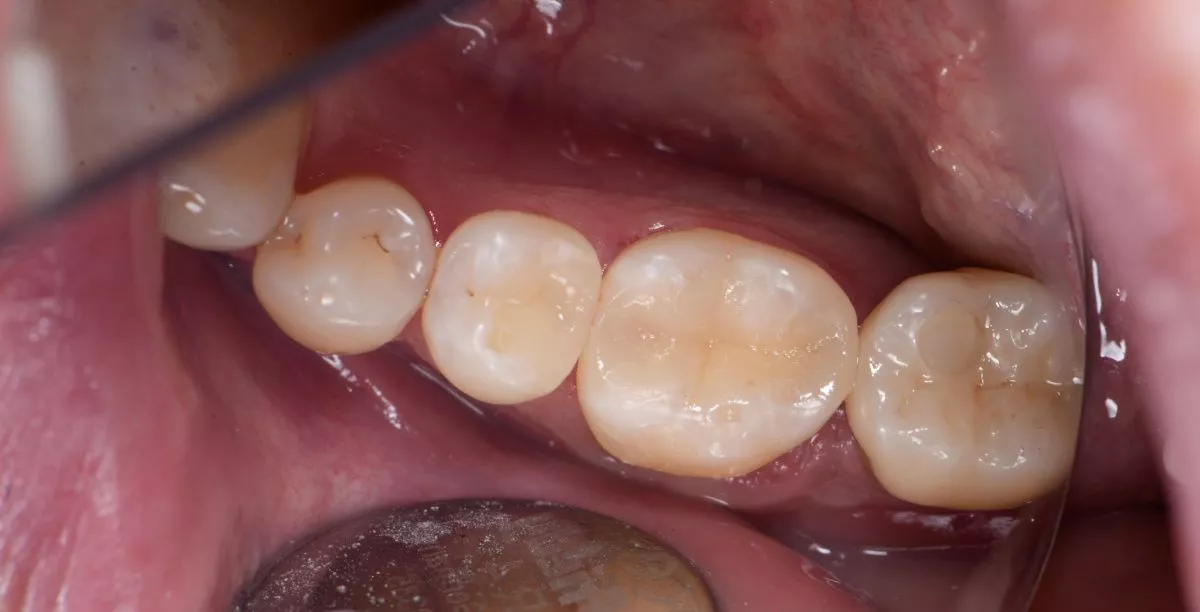

Лечение скрытого кариеса под старой пломбой

Лучшие стоматологические клиники. Лечение скрытого кариеса под старой пломбой  - после процедуры